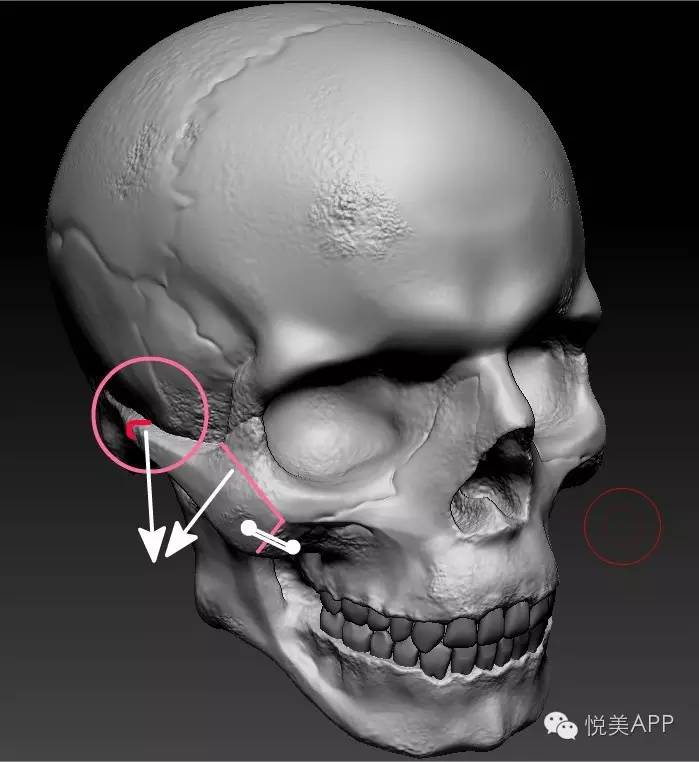

颧骨颧弓内推的极限是多少?

颧骨内推是有一定限度的,颧弓内推的极限决定于颧弓和下颌骨喙突之间的距离,颧弓内推只要不妨碍下颌骨喙突的运动,可以达到极限值。

下颌骨喙突位置:

也就是白色圆圈内的两块骨头距离,推太多会导致张口受限,影响功能